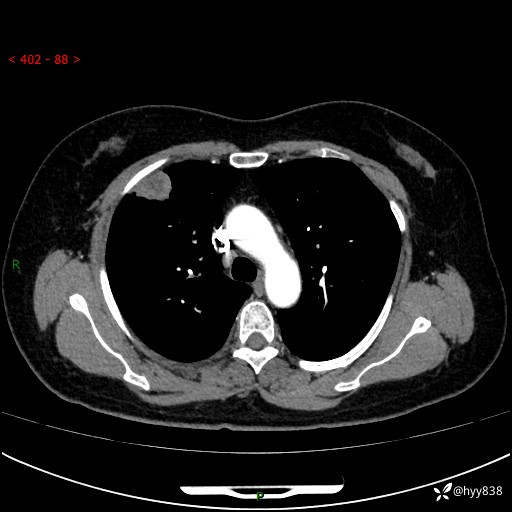

现病史:患者于2天余前无明显出现间断胸痛,无头痛、头晕,无心慌、胸闷、胸痛、呼吸困难、低热、盗汗,无腹痛、腹胀等不适,未进行进一步诊治。于2024.04.14在当地市人民医院行胸部CT检查提示:右肺上叶胸膜下结节。现患者为求进一步诊治,来我院就诊。以“肺肿物”收入我科。 患者自起病以来,精神可,睡眠可,饮食可,大小便正常,体重无明显改变。

胸部CT增强(肺窗,外院平扫)